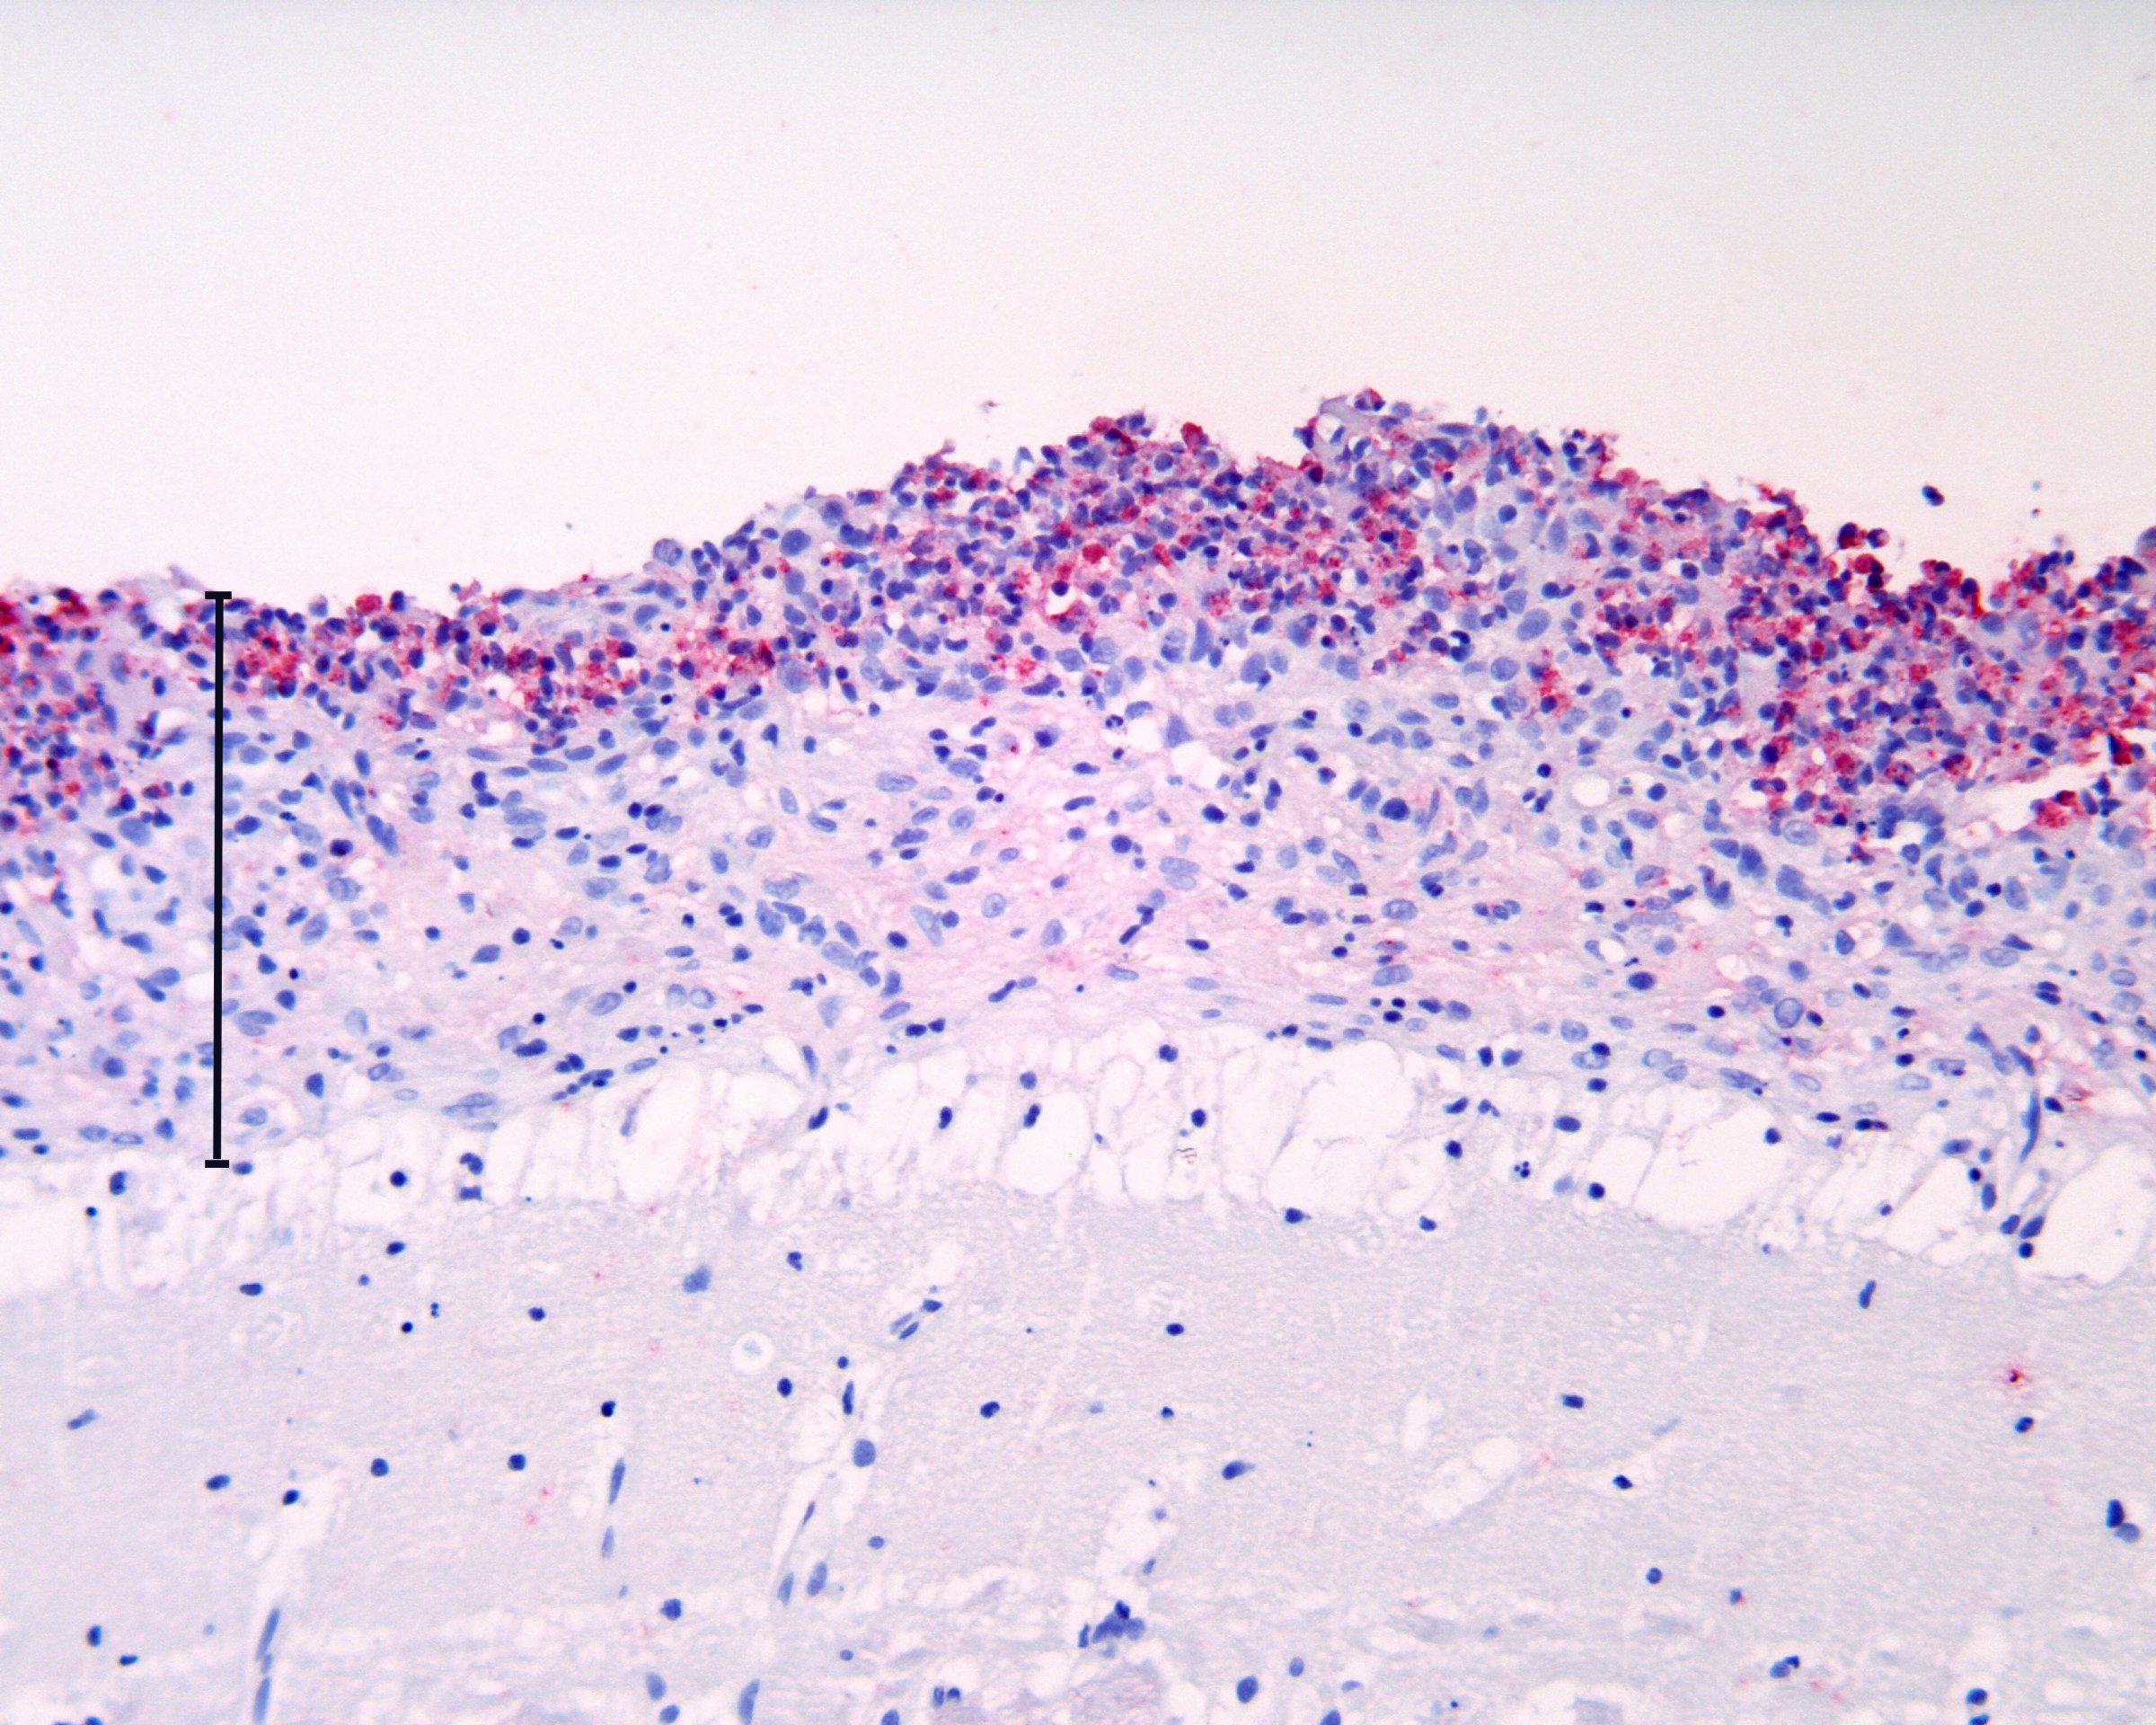

BKD skyldes infeksjon med bakterien Renibacterium salmoniarum. Bakterien vokser seint, og det kan gå lang tid fra fisk blir smitta til de viser kliniske tegn. BKD er listeført nasjonalt i kategori F, og mistanke om eller påvisning av BKD skal umiddelbart meldes til Mattilsynet. Veterinærinstituttet skal bekrefte alle mistanker i egenskap av å være nasjonalt referanselaboratorium for fiskesjukdommer.